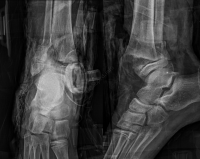

Exemples de décollements épiphysaires Salter 2